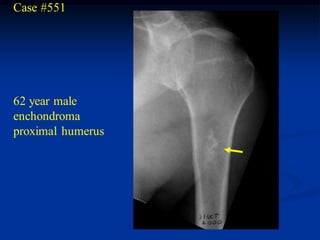

Case #551

62 year male

enchondroma

proximal humerus